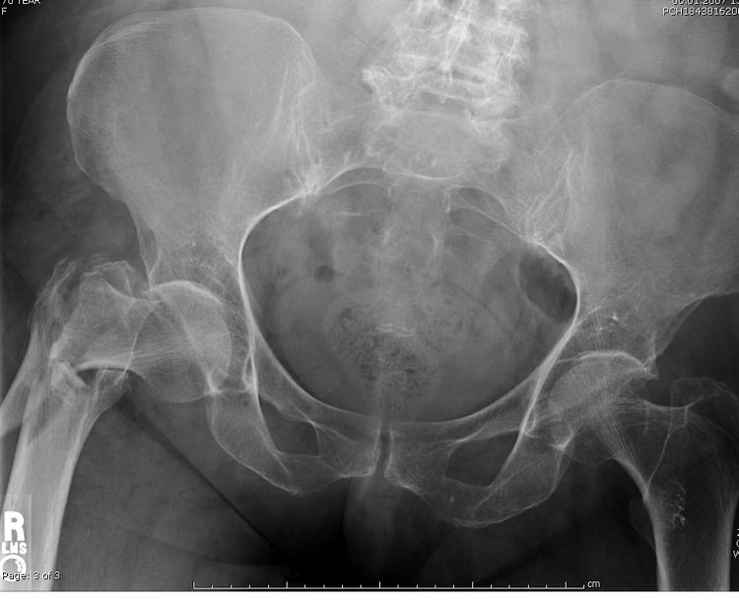

По нашему мнению линия перелома проходит вверху через латеральный отдел шейки бедра, вертельная область состоит из нескольких фрагментов. В таких условиях применить DHS или дистальную бедренную пластину LCP представляется нам сомнительным. Закрытый остеосинтез проксимальным гамма-гвоздем или PFNa невозможен т.к. нет ЭОПа.

Прилагаю Р-ы на вытяжении.

Думаю что перелом всетаки оскольчатый межвертельный, скорее всего использовали бы реконструктивный штифт, но возможно и DHS.

Перелом, на мой взгляд, все-таки чрезподвертельный. Учитывая оскольчатый характер перелома вертельной области, вполне можно рассматривать в качестве альтернативы остеосинтез фиксатором с угловой стабильностью (блокируемая пластина для дистального конца контрлатеральной бедренной кости, производство Синтез или аналог). Конечно, срок ходьбы на костылях будет подольше. Зато картинка посимпатичнее.